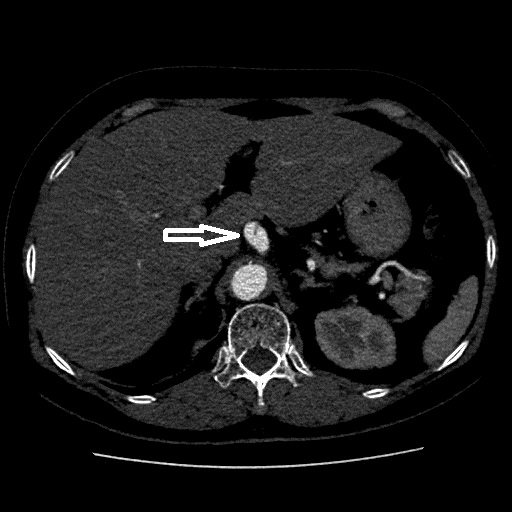

Bệnh nhân P.H, 64 tuổi, ở Cao Nhân, Thủy Nguyên, Hải Phòng tối trước ngày vào viện xuất hiện đau bụng thượng vị dữ dội, đau xuyên ra sau lưng , đau âm ỉ liên tục, thỉnh thoảng trội cơn. Với tiền sử tăng huyết áp, đái tháo đường type 2 nhiều năm đang điều trị, hẹp động mạch vành 50% LAD1, hẹp 40% RCA II, sau khi thăm khám kỹ càng, tiên lượng các yếu tố, nghĩ nhiều đến nguyên nhân đau bụng do nhóm bệnh lý mạch máu gây ra, các bác sỹ đã chỉ định chụp MSCT ổ bụng và phát hiện động mạch thân tạng của bệnh nhân bị lóc tách nội mạc, phình hình thoi kích thước 12mm trên đoạn dài 20mm. Đồng thời qua siêu âm tim cho thấy giảm vận động 2/3 thành bên, thành trước, thành sau thất trái về phía đáy mức độ vừa, chức năng tâm thu thất trái giảm EF 33%. Các sĩ Bệnh viện đa khoa Quốc tế Hải Phòng chẩn đoán người bệnh Phình tách động mạch thân tạng cấp tính trên nền Suy tim EF giảm, bệnh tim thiếu máu cục bộ, tăng huyết áp, Đái tháo đường type 2, RLMM, Suy thận mạn.

- Phình tách hình thoi động mạch thân tạng kích thước 12 x 20mm